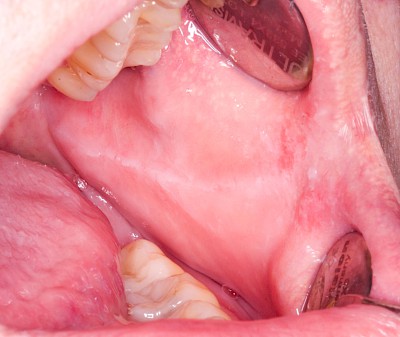

Blutpunkte (z.B. Petechien), Blutblasen (z.B. Hämangiome) & rote Flecken (z.B. Ausschlag) haben in der Regel eine längere Entstehungsgeschichte und sind häufig nicht auf eine direkte kurzzeitig zurückliegende Verletzung zurückzuführen.

Besonders häufig läßt sich eine starke Gefäßzeichnung unter der Zunge beobachten.

Beispiele8 Bilder

Kauen auf Wange, Zunge & Lippen

Das Kauen auf Wange, Zunge oder Lippen zählt zu den sogenannten Habits und ist meist stressbedingt. Diskrete Linien (Verhornungsleisten) oder aber unruhige Schleimhautareale bis hin zu Erscheinungsformen wie "wildes Fleisch" können dabei auffallen.

Beispiele32 Bilder